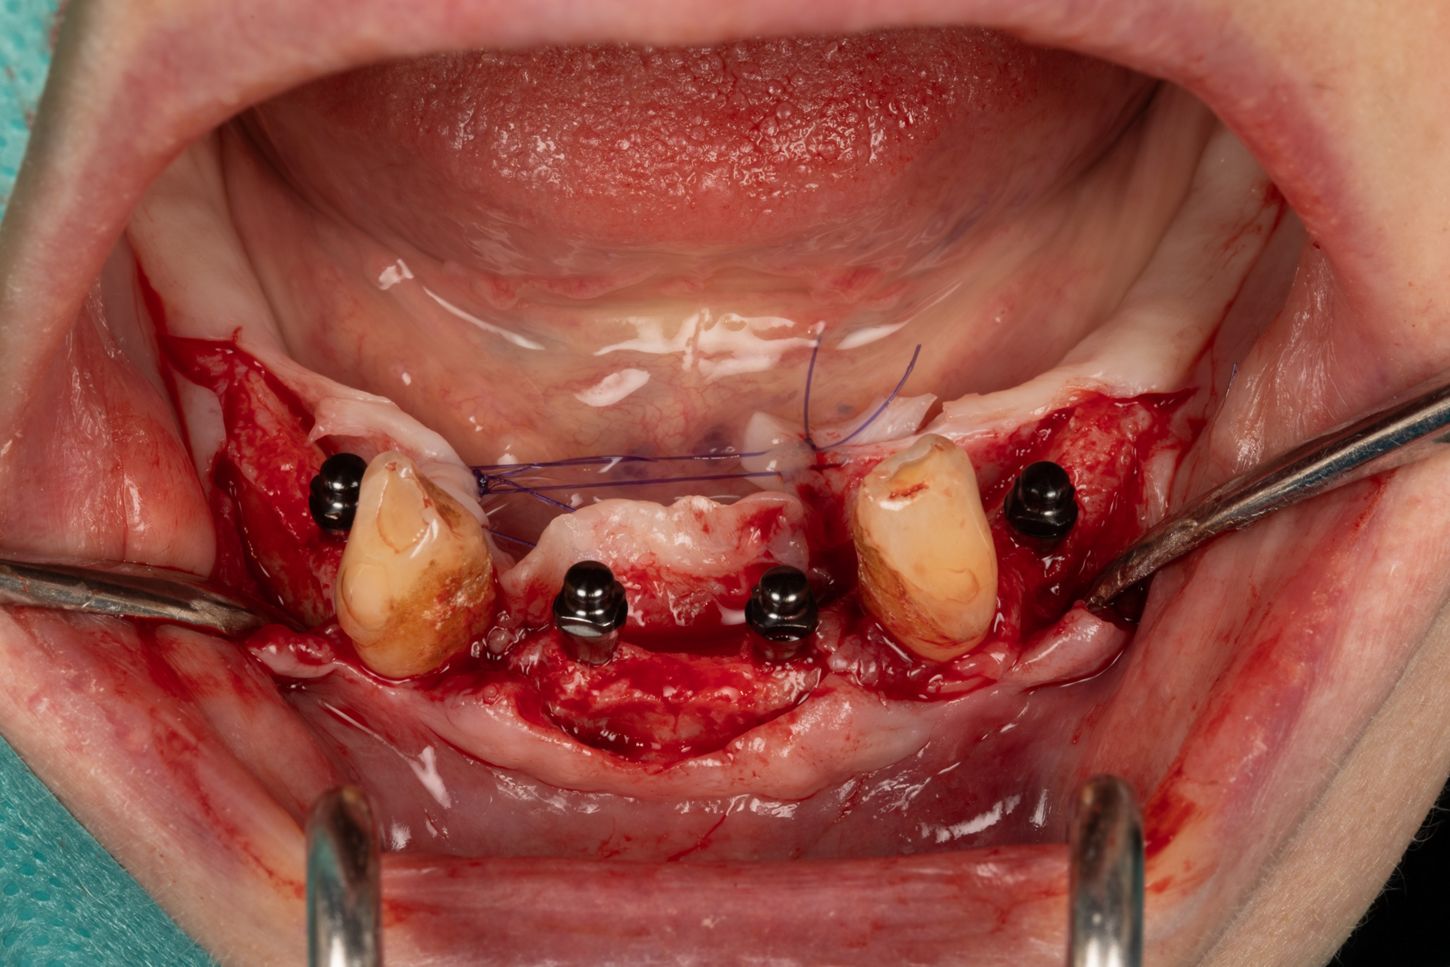

3c. Two mini-implants with a diameter of 2.6 mm and a length of 12 mm were placed in positions 32 and 42, first manually and then using a contra-angle. The insertion torque recorded at the end of the procedure was 21 N.cm in 32 and 17 N.cm in 42. The implants were positioned 0.5 mm subcrestal, i.e. with slight burial of the smooth neck.

3c

3d

3d. Two mini-implants with a diameter of 2.6 mm and a length of 12 mm were placed in positions 34 and 44 using the same protocol as for the previous mini-implants. The torque obtained was 27 Ncm in 34 and 37 Ncm in 44.

3e. Canines 33 and 43 were extracted and the burial of the implants was then checked.

3e

3f. 5/0 absorbable sutures were placed around the mini implants, taking care to preserve as much keratinised tissue as possible around the Optiloc attachments.

3f